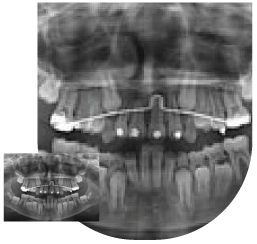

Maxilofacial

En pacientes adultos con una importante alteración en la estética y la anomalía facial. La solución es un tratamiento combinado de ortodoncia y cirugía ortognática. El tratamiento de ortodoncia con brackets sirve para preparar la boca, para que el cirujano coloque los maxilares en su posición. Una vez realizada la cirugía. Con los brackets terminaremos de ajustar los dientes en una correcta oclusión.